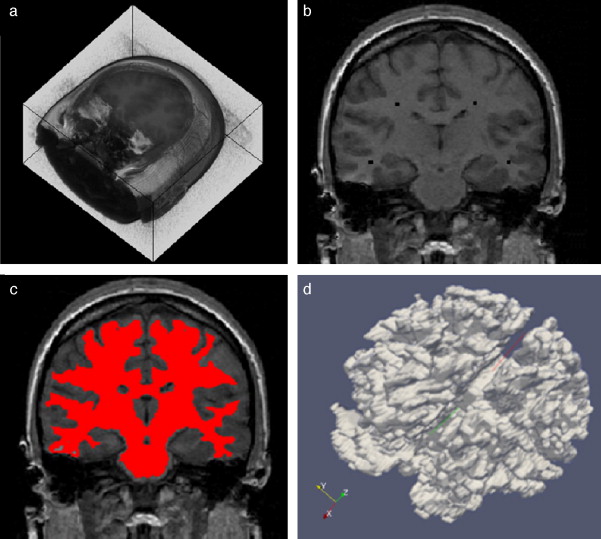

En la figura 10 se presenta el resultado de segmentar la materia blanca del cerebro en IRM empleando la rutina de Region Growing mencionada. En la figura 10 .a se observa la vista 3D del volumen inicial. En la figura 10 .b se observa uno de los cortes de la figura 10 .a con la selección de cuatro semillas iniciales de forma esférica dentro de la zona de la materia blanca. En la figura 10 .c se observa en color rojo la zona región de la materia blanca obtenida al finalizar la rutina de segmentación. En la figura 10 .d se presenta una vista 3D de la zona de la materia blanca segmentada.

Segmentación de materia blanca empleando Region Growing en IRM del cerebro. (a) ...

Figura 10.

Segmentación de materia blanca empleando Region Growing en IRM del cerebro. (a) Volumen formado por varios cortes de IRM cerebral original. (b) Vista de un corte coronal con la lección de cuatro semillas iniciales. (c) Vista del corte coronal (b) con la materia blanca segmentada con Region Growing . (d). Vista volumétrica de la materia blanca segmentada en (c).